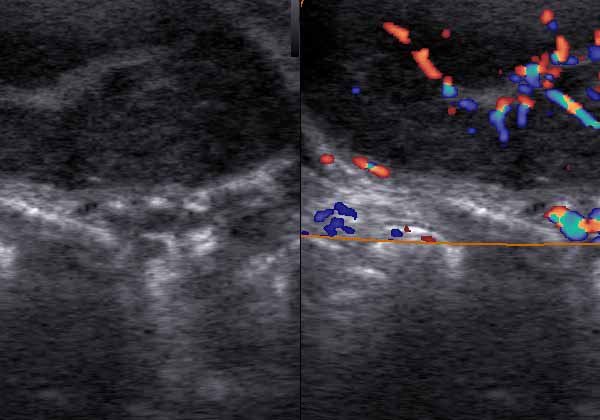

– الموجات فوق الصوتية بالأبيض والأسود (فحص دماغ الطفل والأعضاء الداخلية) ،

– الموجات فوق الصوتية دوبلر الملونة (فحص الأوعية الدموية للطفل والأم)